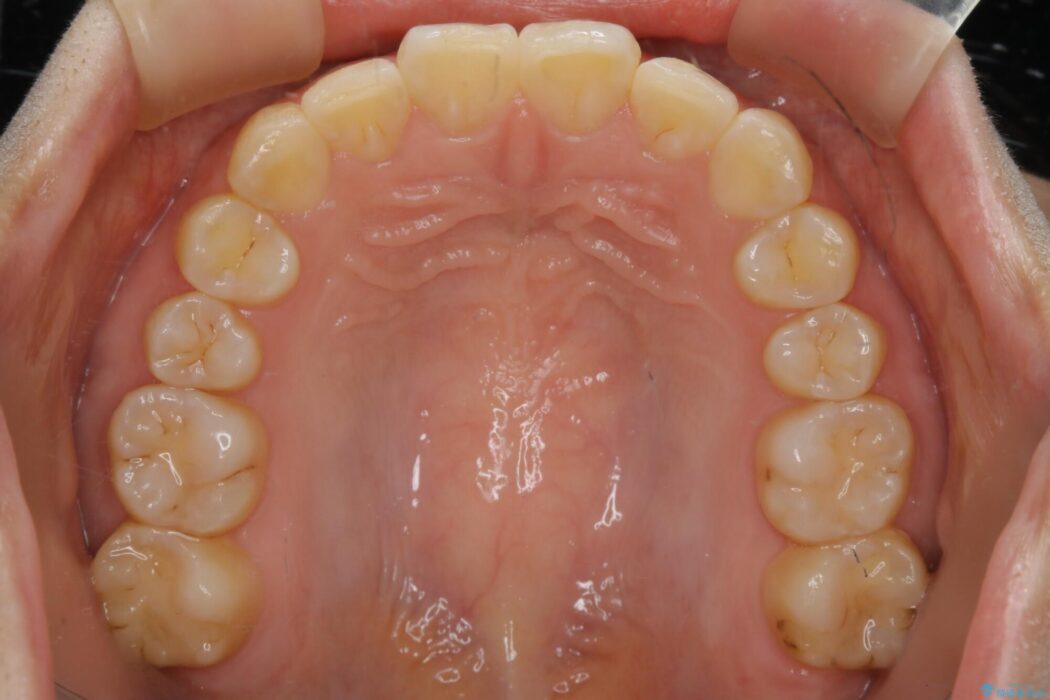

噛み合わせの違和感と前歯のガタガタを主訴に来院されました。

歯軸傾斜と軽度の叢生が見られましたので、通常の位置へと傾きを戻し少量の遠心移動に加えアーチ(歯列弓)の拡大とIPRを施すことで改善していく非抜歯での治療計画としました。